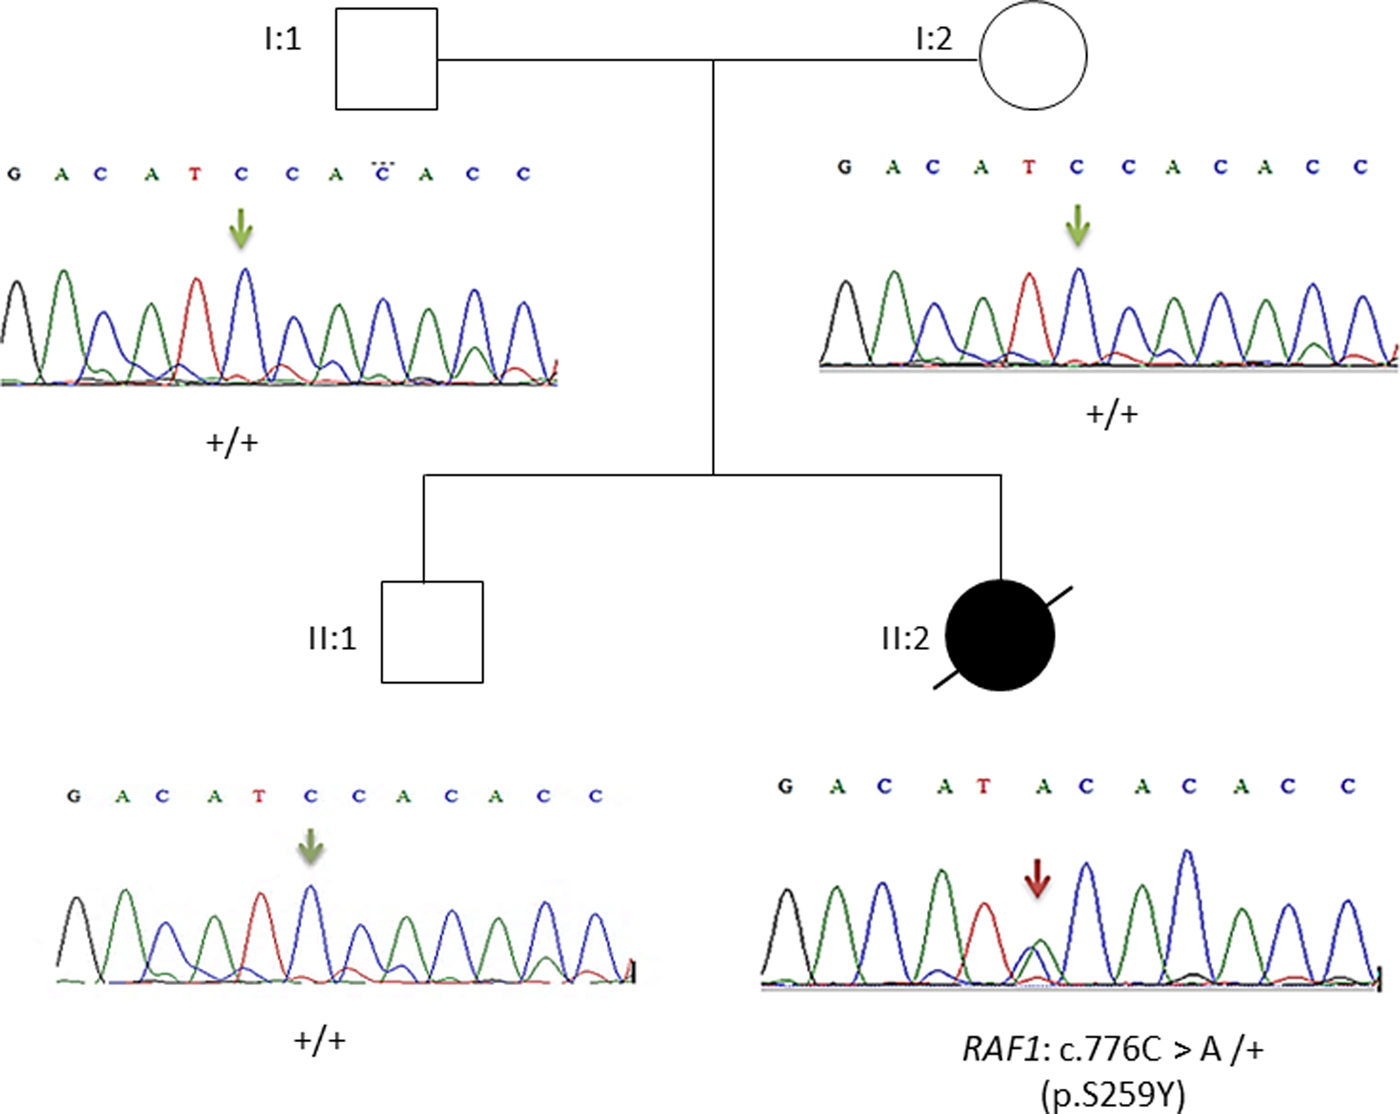

By focusing on 20 genes of the RAS/MAPK pathway, only one exonic variant in exon 7 of the RAF1 gene was found. All remaining variants were intronic. All variants in the RAS/MAPK genes identified in the affected child are listed in the Supplementary Material (second sheet). The RAF1: c.776C > A; p.Ser259Tyr missense variant occurred de novo. The genomic coordinates of this variant in the human assembly GRCh37/hg19 is chr3:12,645,693-12,645,693.

This result as well as the mode of transmission were validated by Sanger sequencing. The electropherograms shown in Figure 3 confirmed the p.Ser259Tyr mutation and the mode of inheritance.

Fig. 3. Pedigree of the family. Affected proband is denoted by filled circle, unaffected members are denoted by empty symbols. Sequence electropherograms are shown below symbols. (+) indicates the wild-type allele, the arrow indicates the position of the mutation.

Overall, the heterozygous RAF1 p.Ser259Tyr variant identified by WES confirms the diagnosis of Noonan syndrome in our patient.